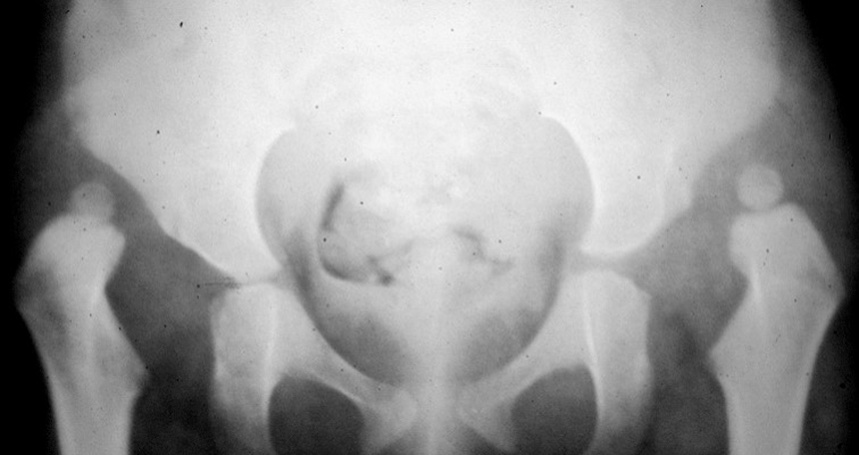

L’esame ecografico è stato introdotto negli anni 80 da Graf che ha proposto una classificazione in quattro tipi per valutare condizioni di immaturità dell’anca (Tipo II) e condizioni più gravi come la sublussazione (Tipo III) e la lussazione franca (Tipo IV) 5. Il metodo è basato sulla valutazione dell’entità di due angoli: l’angolo α formato dalla linea di base che è rappresentata dalla continuazione verso il basso del profilo laterale dell’ala iliaca e la linea del tetto osseo mentre l’angolo β è formato sempre dalla linea di base e la linea del tetto cartilagineo. La radiografia dell’anca può essere attualmente utilizzata con lo scopo di confermare la diagnosi dopo i 4-6 mesi di vita. Nei casi di displasia è presente la caratteristica triade di Putti caratterizzata dalla sfuggenza del tetto acetabolare, dal ritardo di comparsa o dall’ipoplasia del nucleo di ossificazione della testa femorale che rappresentano segni di ritardo dell’ossificazione acetabolare e dall’allontanamento/risalita dell’epifisi prossimale del femore che viene valutata attraverso interruzione dell’ogiva o arco di Shenton. Tale ogiva è formata dal margine mediale della metafisi femorale che, in condizioni di normalità, si continua con il margine inferiore della branca ileo-pubica (Fig. 5).